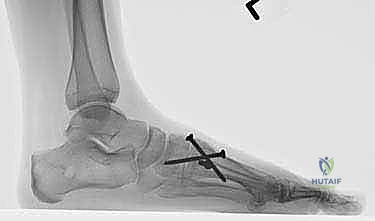

5. التثبيت الداخلي (Internal Fixation)

بعد التأكد من المحاذاة المثالية، يتم تثبيت العظام بشكل دائم. يستخدم الأستاذ الدكتور محمد هطيف أحدث التقنيات العالمية في التثبيت، والتي تشمل عادة مسامير تيتانيوم متقاطعة (Crossed Screws) أو شريحة معدنية متخصصة مع مسامير (Plating System) لضمان أقصى درجات الثبات والضغط بين العظمتين، مما يسرع من عملية الالتئام.

- المتابعة الإشعاعية: يتم إجراء أشعة سينية للتأكد من بدء التحام العظام.

- تحمل الوزن: إذا كانت الأشعة مطمئنة، يُسمح بالانتقال التدريجي لتحميل الوزن الكامل أثناء ارتداء الحذاء الطبي، ثم الانتقال لاحقاً إلى حذاء رياضي واسع ومريح.